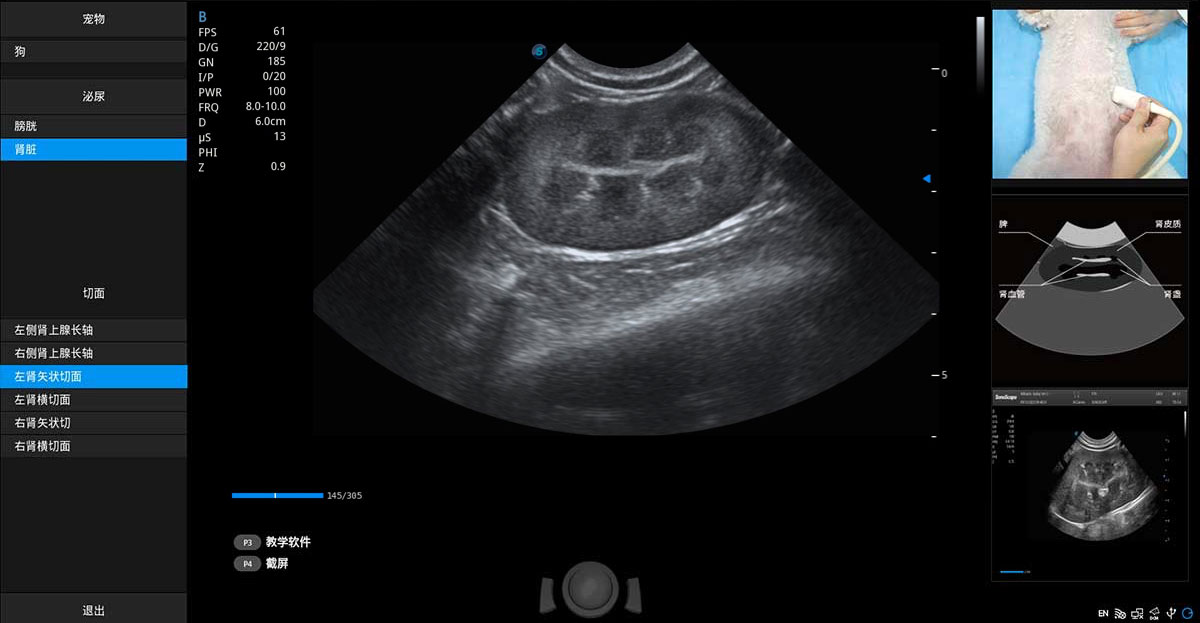

提供解剖示意圖、標(biāo)準(zhǔn)超聲圖像、掃查手法涂和操作者實時檢查圖像,指導(dǎo)操作者進(jìn)行標(biāo)準(zhǔn)切面的正確掃查。

ProPet 80 專為動物醫(yī)生設(shè)計,對不同的動物體型和生理結(jié)構(gòu)作出了針對性的優(yōu)化。通過動物影像專用軟件,可滿足個性化的應(yīng)用需求,幫助動物醫(yī)生獲得更精確的診斷數(shù)據(jù)。